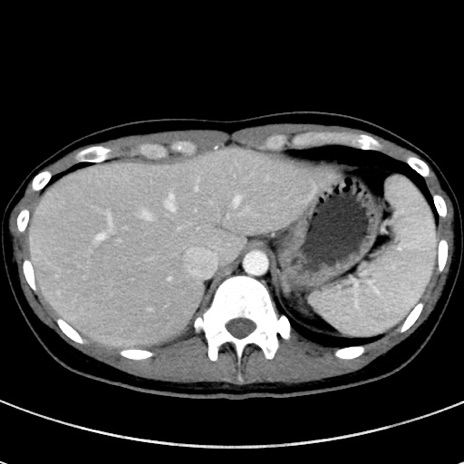

症例17(横断像)

【症例】20歳代女性

【主訴】嘔吐、下腹部痛

【現病歴】昨日夕食後に嘔吐し下腹部痛が出現。本日になっても嘔吐持続し改善しないため来院。

【身体所見】意識清明、BT 37.2℃、BP 108/67mmHg、腹部:平坦、やや硬、下腹部正中から右にかけて圧痛あり、反跳痛軽度あり、tapping pain(+)。

【データ】WBC 13600、CRP 14.94